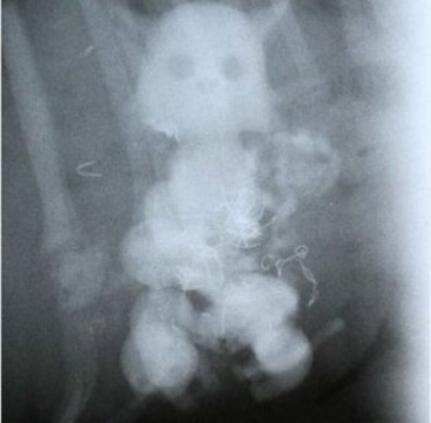

Idoso foi internado nesta semana, em Sorriso (420 km ao norte de Cuiabá), após ficar com uma boneca de plástico presa no ânus. Após atendimento médico, o paciente conseguiu expelir o brinquedo e a cirurgia não foi necessária.

Conforme noticiado pelo portal JK Notícias, após passar mal, o homem procurou a Unidade de Pronto Atendimento (UPA) para remoção do objetivo de cerca de 20 centrímetros.

Após o primeito atendimento médico, ele foi prontamente encaminhado para o Hospital Regional de Sorriso, devido à possibidade de operação, que depois foi descartada.

Paciente ficou internado até a última quarta-feira (5), enquanto esperava pela cirurgia, mas o objeto acabou expelido naturalmente, sem a necessidade de procedimentos.